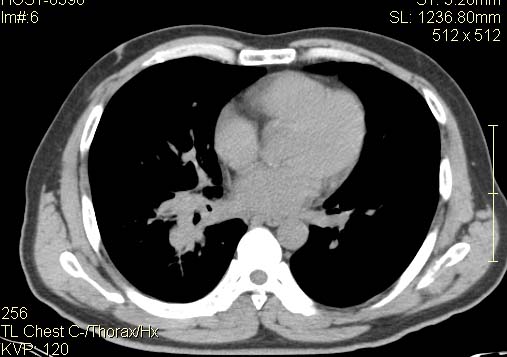

以下是引用qingyuan在2007-4-17 14:19:00的发言:[br]右肺下叶外侧后段胸膜下区节结样病变、分叶、内可见空洞,壁厚薄不均,胸膜凹陷、肺门周围区纹理增粗、僵硬、并近似小结节样改变,肺门区软组织节结、纵膈淋巴结肿大,患者病史长、抗炎治疗无好转炎性改变基本排除,考虑:右肺下叶周围型肺癌伴纵膈及右肺门区淋巴结转移、肺内淋巴管受侵。